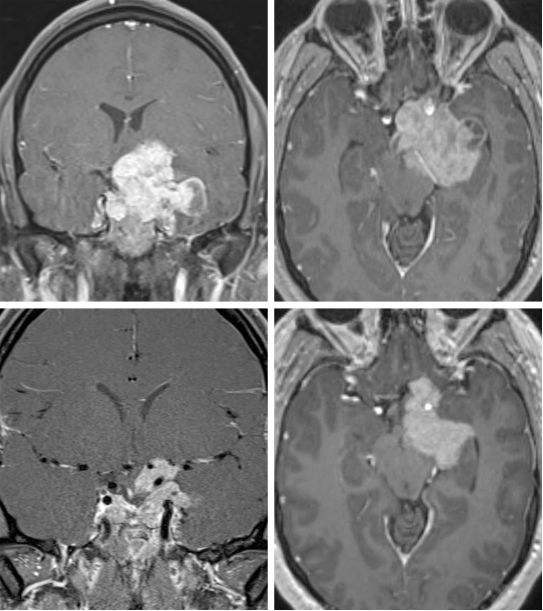

图4. 一位年轻的偏侧非对称垂体大腺瘤患者,曾行扩大经鼻蝶入路垂体瘤切除术(上图)。由于外侧术野盲区及肿瘤质地,蝶鞍后方及外侧部分肿瘤通过经鼻蝶入路难以切除。完成鞍上肿瘤减压后,残余肿瘤仍引起视神经及脑干压迫,限制了术后放疗的效果(下图)。翼点入路适用于此情况下视神经及脑干的进一步减压。二次手术行肿瘤部分切除和视神经减压,但肿瘤包膜与周围组织粘连紧密,未强行切除,残留部分肿瘤组织,保护穿支血管。